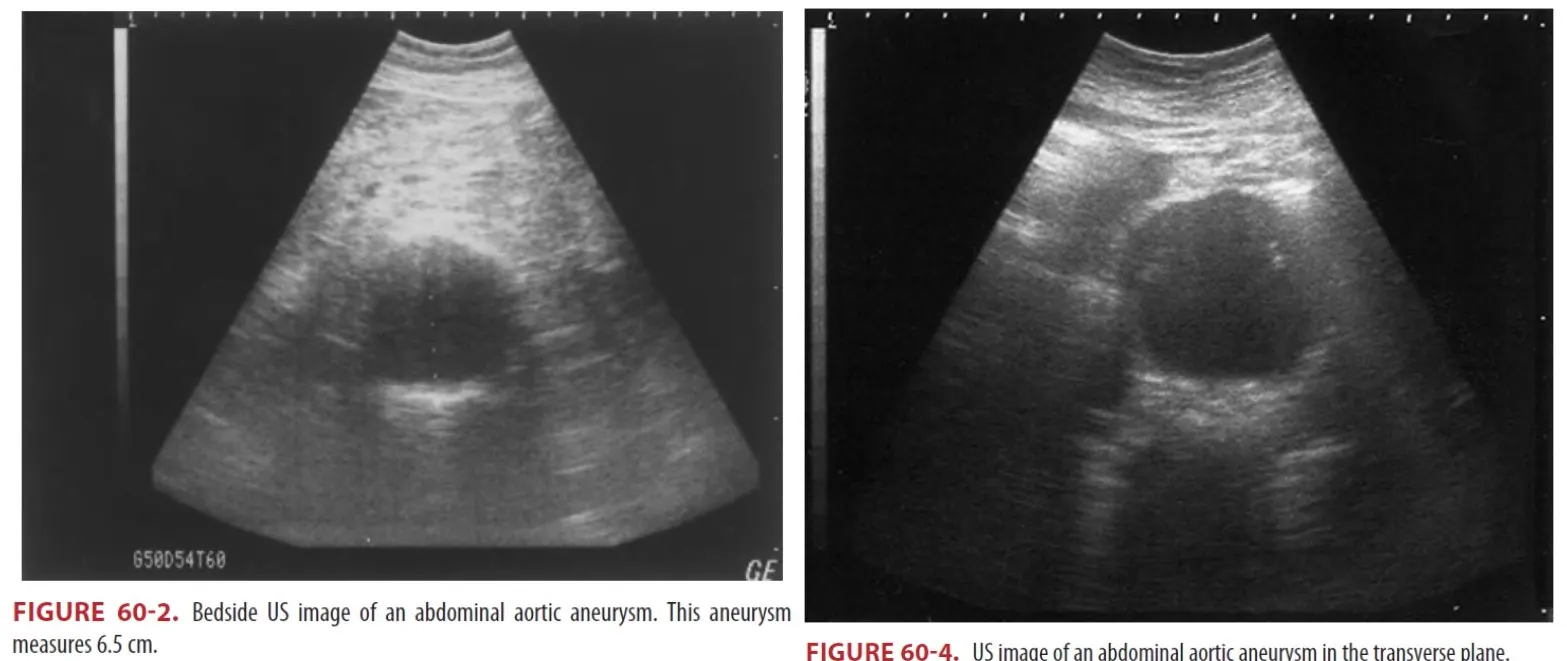

(1) Unstable한 환자의 경우 응급실을 나가서는 안 되고 bedside US가 image of choice이다.

① Bedside US는 ideal initial screening.

② Aneurysm을 확인하고 크기를 평가하는데 90% 초과의 민감도를 가짐

③ 3cm 미만의 aortic diameter는 acute aneurysmal disease를 배제할 수 있다.